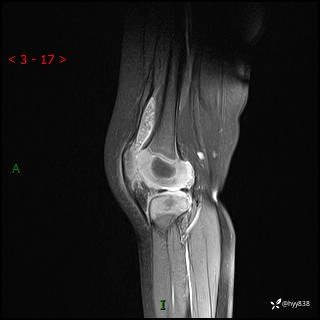

现病史:患儿1月前无明显诱因出现左下肢跛行,伴左膝关节红肿,无发热、咳嗽、恶心、呕吐等症,于当地医院就诊行X线片未提示异常,今至我院门诊就诊,门诊医师拟“跛行待查”收入院。 病后,患儿精神、食欲可,睡眠欠安,大小便通畅,体力体重无明显下降。

左膝MRI平扫